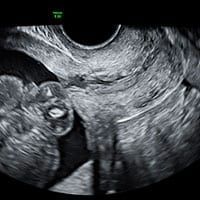

The Viability Scan is the first scan in your pregnancy journey. It is sometimes referred to as the “dating scan” or “early pregnancy scan”.

Viability Scan/Dating Scan

If you are planning to have NIPT, viability scan will help you to see how many babies you have and establish proper dating for earliest NIPT appointment.